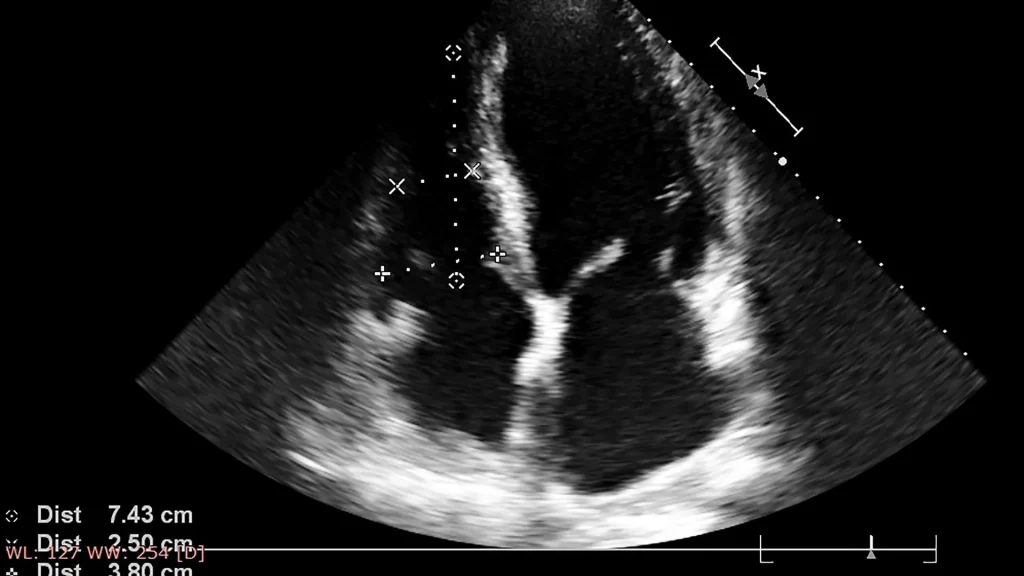

Pemanfaatan AI sangat bermanfaat dalam mendeteksi kelainan pada organ vital seperti jantung, hati, dan ginjal. AI membantu memperlihatkan area yang mencurigakan sehingga dokter dapat fokus pada pemeriksaan lebih lanjut. Hal ini meningkatkan peluang diagnosis dini penyakit serius.

AI pada ultrasound juga dimanfaatkan untuk mengidentifikasi adanya tumor atau lesi pada jaringan tubuh. Sistem dapat membedakan antara jaringan normal dan abnormal dengan tingkat akurasi yang tinggi. Hal ini mendukung penentuan langkah medis yang lebih tepat.